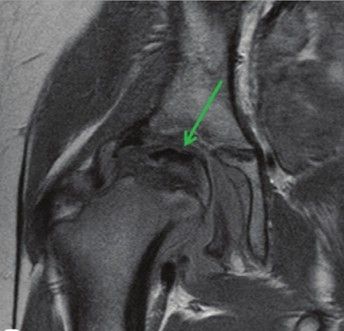

Магнитно-резонансная томография (МРТ)

В начале первой (аваскулярной) стадии нарушается кровоснабжение головки бедра и начинает отмирать костная ткань, на фоне чего у ребёнка появляется хромота. На этой стадии на МРТ могут быть обнаружены участки некроза — как правило, в субхондральной зоне (непосредственно под хрящевой поверхностью). Кроме того, на МРТ видно уменьшение размеров и/или отсутствие нормального роста головки бедренной кости, что может быть определено даже на ранних сроках.

![Изображение МРТ правого тазобедренного сустава у девятилетней девочки с болезнью Пертеса: низкий сигнал (зелёная стрелка), который свидетельствует о некрозе [19] Изображение МРТ правого тазобедренного сустава у девятилетней девочки с болезнью Пертеса: низкий сигнал (зелёная стрелка), который свидетельствует о некрозе [19]](/media/bolezny/bolezn-pertesa/izobrazhenie-mrt-pravogo-tazobedrennogo-sustava-u-devyatiletnyay-devochki-s-boleznyu-pertesa-nizkiy-signal-zelyonaya-strelka-kotoryy-svidetelstvuet-o-nekroze-19_s.jpeg)

Изображение МРТ правого тазобедренного сустава у девятилетней девочки с болезнью Пертеса: низкий сигнал (зелёная стрелка), который свидетельствует о некрозе [19]

На стадиях реваскуляризации (восстановления кровоснабжения костной ткани) и заживления, которые длятся в течение многих лет, сигнал костного мозга обычно неоднородный. Хорошим прогностическим признаком будет усиление сигнала в боковых отделах головки бедренной кости [19].